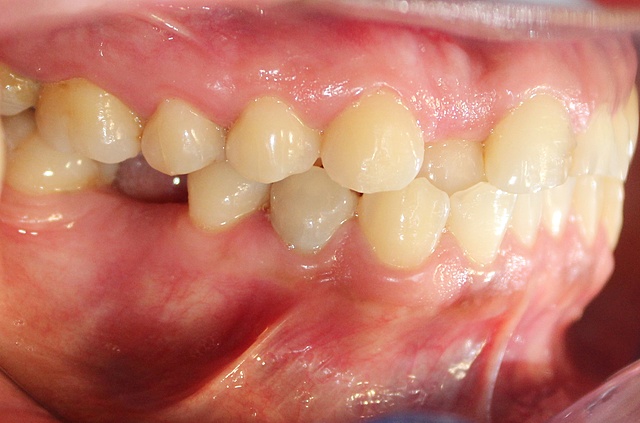

• Análisis intraoral

Análisis intraoral

Se encontró un apiñamiento leve, restauración filtrada en OD 1.1 y 2.1. Caries en OD 1.2, 1.5 1.6, 1.7, 1.8, 2.2, 2.4, 2.5, 2.6, 2.7, 3.4, 3.5, 3.8, 4.5, 4.7 y 4.8. Ausencia de OD 3.6, 3.7 y 4.6.

• Análisis oclusal

Análisis oclusal

Clase de Angle:clase canina I derecha y clase canina I izquierda, ausencia de primeros molares inferiores para establecer clase molar.